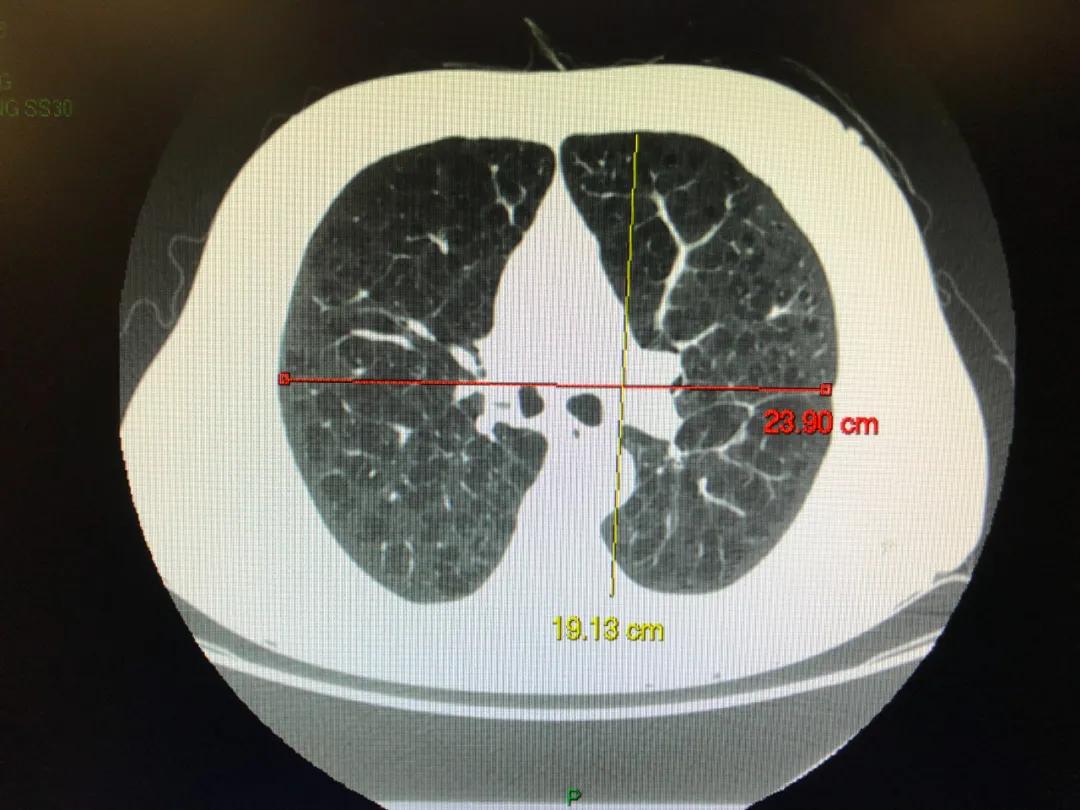

图为该患者胸部CT特殊成像方式, 图中红色部分显示双肺多发不均匀性肺气肿

该患者近3年憋气症状加重,就是跟他的肺气肿有关系。通过该患者的胸部CT也可以看出患者是不均匀型的肺气肿,也就是不同肺叶的肺气肿轻重不一。